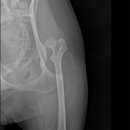

• 24시 에피소드 동물 메디컬 센터 | 만촌동 동물병원 강아지 요골·척골 골절 수술 후기 [24시에피소드동물메디컬센터]

만촌동 동물병원 강아지 요골·척골 골절 수술 후기 [24시에피소드동물메디컬센터] 만촌동 동물병원 ​ 안녕하세요. ​ 풍부한 경험과 따듯한 진료를 바탕으로, 반려동물의 건강하고 행복한 하루하루를 함께 만들어 가는 만촌동 동물병원 24시에피소드동물메디컬센터 입니다. 24시에피소드동물메디컬센터 대구광역시 동구...

에피소드동물메디컬센터(2025-06-26 12:41:00)